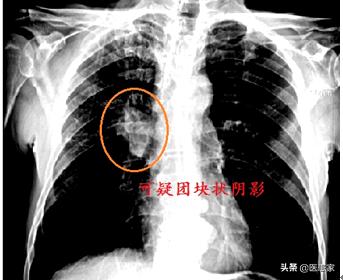

En fait, les données épidémiologiques du monde entier et de notre pays montrent que, tant en Chine que dans d'autres pays du monde, l'incidence des néoplasmes malins et les taux de morbidité et de mortalité ont augmenté de manière significative (bien sûr, chaque néoplasme malin peut être très différent, et nous parlons ici de la tendance générale des néoplasmes malins). En particulier, de plus en plus de personnes se voient diagnostiquer des tumeurs malignes, telles que le cancer du poumon, le cancer de la thyroïde, le cancer de l'estomac, etc., ce qui affecte sérieusement la qualité de vie des patients et réduit même leur espérance de vie. Pourquoi y a-t-il de plus en plus de tumeurs malignes ? Le Dr Zhang résume que cela peut être lié aux facteurs suivants.

Par exemple, l'apparition d'un cancer du poumon chez une personne de plus de 40 ans peut être liée à son tabagisme prolongé, mais aussi à la mutation de ses gènes ou, plus probablement, au tabagisme des gènes à l'origine de la mutation.

Le fait est que chaque personne est différente, que chaque tumeur est différente et que, selon la stadification, la tumeur se développera à un rythme différent. Dans certains cas, la tumeur se développera plus rapidement, avec une forte croissance en quelques mois, alors que dans d'autres cas, elle ne se développera que très peu en trois à cinq ans. Cependant, la raison pour laquelle le grand public peut avoir l'impression que la tumeur se développe très rapidement est simplement qu'après la détection, de nombreuses personnes sont généralement à un stade intermédiaire ou même à un stade avancé, ce qui fait que les gens ont souvent l'impression d'être pris au dépourvu entre le moment de la détection et le moment où ils ne sont plus en vie.

Je voudrais dire ici que lorsque le cancer est à un stade précoce, son développement n'est généralement pas très rapide, le traitement est simple et le pronostic est meilleur. Cependant, la raison pour laquelle de nombreuses personnes découvrent que le cancer est à un stade avancé est qu'elles ne prêtent généralement pas attention aux examens médicaux lorsqu'elles ne se sentent pas mal, qu'elles ne passent pas d'examens médicaux pendant trois à cinq ans et qu'elles ne pensent à se rendre à des examens que lorsque des symptômes gênants apparaissent. Cependant, lorsque les symptômes apparaissent, ils ont souvent manqué la meilleure période de traitement.